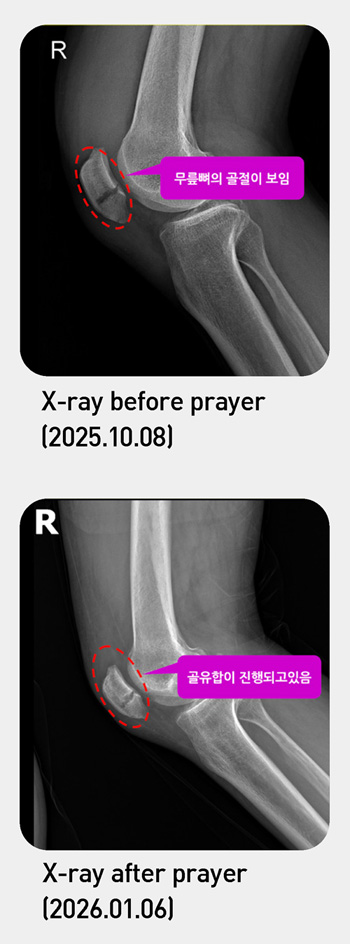

Healed from a knee fracture in six days

On Wednesday, October 8 last year, during the Chuseok holiday, I went hiking with my family for the first time in a while. About fifteen minutes after we began the hike, my left ankle caught on a sharply protruding rock, and I fell. I tried to get back up and continue climbing, but the intense, stabbing pain in my knee made it impossible to take even a single step, so I had no choice but to come back down the mountain. The descent was far more painful than the climb. Supporting myself with both hands on the ground, I barely managed to make my way down the mountain on one leg and finally got into a taxi. The moment I touched my knee in the taxi, I could clearly feel that a bone had been broken. Although I arrived in front of my house, I was unable to take even one step, so I went straight to a nearby private clinic. There, I was immediately told to go to the emergency room of a large hospital. After an MRI scan in the emergency room, the doctor said, “Your kneecap is fractured. Unlike other bones, the kneecap is separated into upper and lower parts, so surgery is absolutely necessary.” And, the doctor recommended that even with surgery, I would need to use crutches and undergo rehabilitation therapy and suggested scheduling the operation for Friday, October 10. However, if I were hospitalized and had the surgery, I would not be able to attend the church’s 43rd Anniversary Service on October 12. Desiring to be healed by faith, I chose not to be hospitalized and returned home. Thereafter, at every Daniel prayer meeting, I deeply repented in prayer for the times I had failed to pursue peace at work and at home, and I received pastor Soojin Lee’s prayer for the sick each day. On October 12, the day of the church anniversary service, my knee pain was so severe that I struggled each time I put my foot down. I arrived early at the anniversary celebration with a wheelchair prepared. As pastor Soojin Lee was entering the celebration hall, she saw me and greeted me with a nod. At that very moment, an indescribable peace filled my heart. After the first service ended, faith was given to me, so I removed the splint and tried sitting without it. To my amazement, there was no discomfort in my leg at all. Then, during the second part of the service?the celebration?I felt prompted to remove the compression bandage as well, so I took it off and tried walking. Astonishingly, at that very moment, my leg didn’t hurt. After all the celebration had ended, as pastor Soojin Lee was heading back, my daughter said to her, “Please pray for my father.” She immediately came over, laid her hand on my knee, and prayed for me. Right after that, I could feel the pain in my knee completely disappear. Next morning, something amazing happened. As usual, I was able to transfer between the bus and subway and go to work normally. On October 14, six days after the fracture, I visited the hospital and took an X-ray. The doctor said, “The bone has almost completely healed. You just need to take good care of it now.” The kneecap, which is more difficult to treat than other bones, had joined together in just a few days. Hallelujah! I give all thanks and glory to God who healed me.